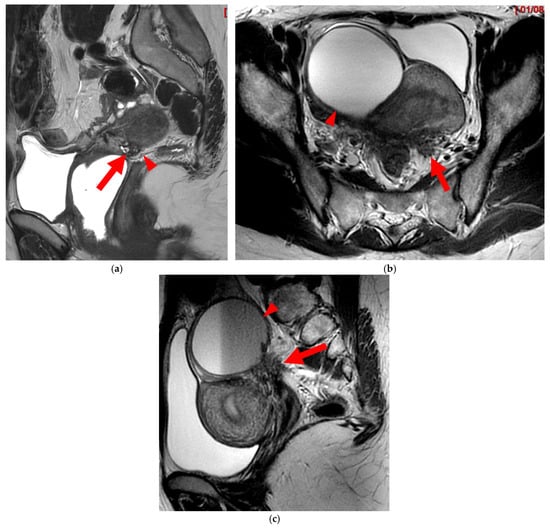

Figure 7. Pelvic MRI scans of two patients with HTD type 5B USLs. (a) Patient 1: sagittal T2WI shows a microcystic nodule (arrow) within the origin of the right USL (arrowhead). (b,c) Patient 2: axial (b) and sagittal (c) T2WI show a nodular left USL with spiculated margins (arrow) and a right ovarian endometrioma (arrowhead).

A type 5B USL (Figure 7) is nodular with spiculated margins. A type 5B USL may also display an isolated nodule with microcystic content.